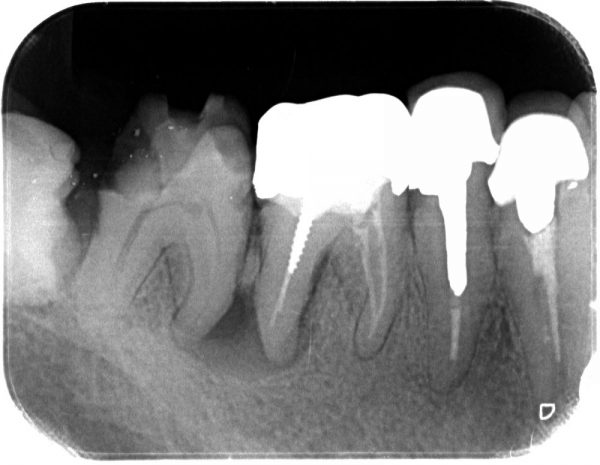

レントゲンをとってみると、根の先に黒い透過像が認められます。

レントゲンをとってみると、根の先に黒い透過像が認められます。

黒くなっているのところは、ものがない状態です。白いところは金属などの放射線を通さないところです。

つまり、この根の先の部分は骨が溶けて薄くなっている状態で、根尖性歯周炎と言います。